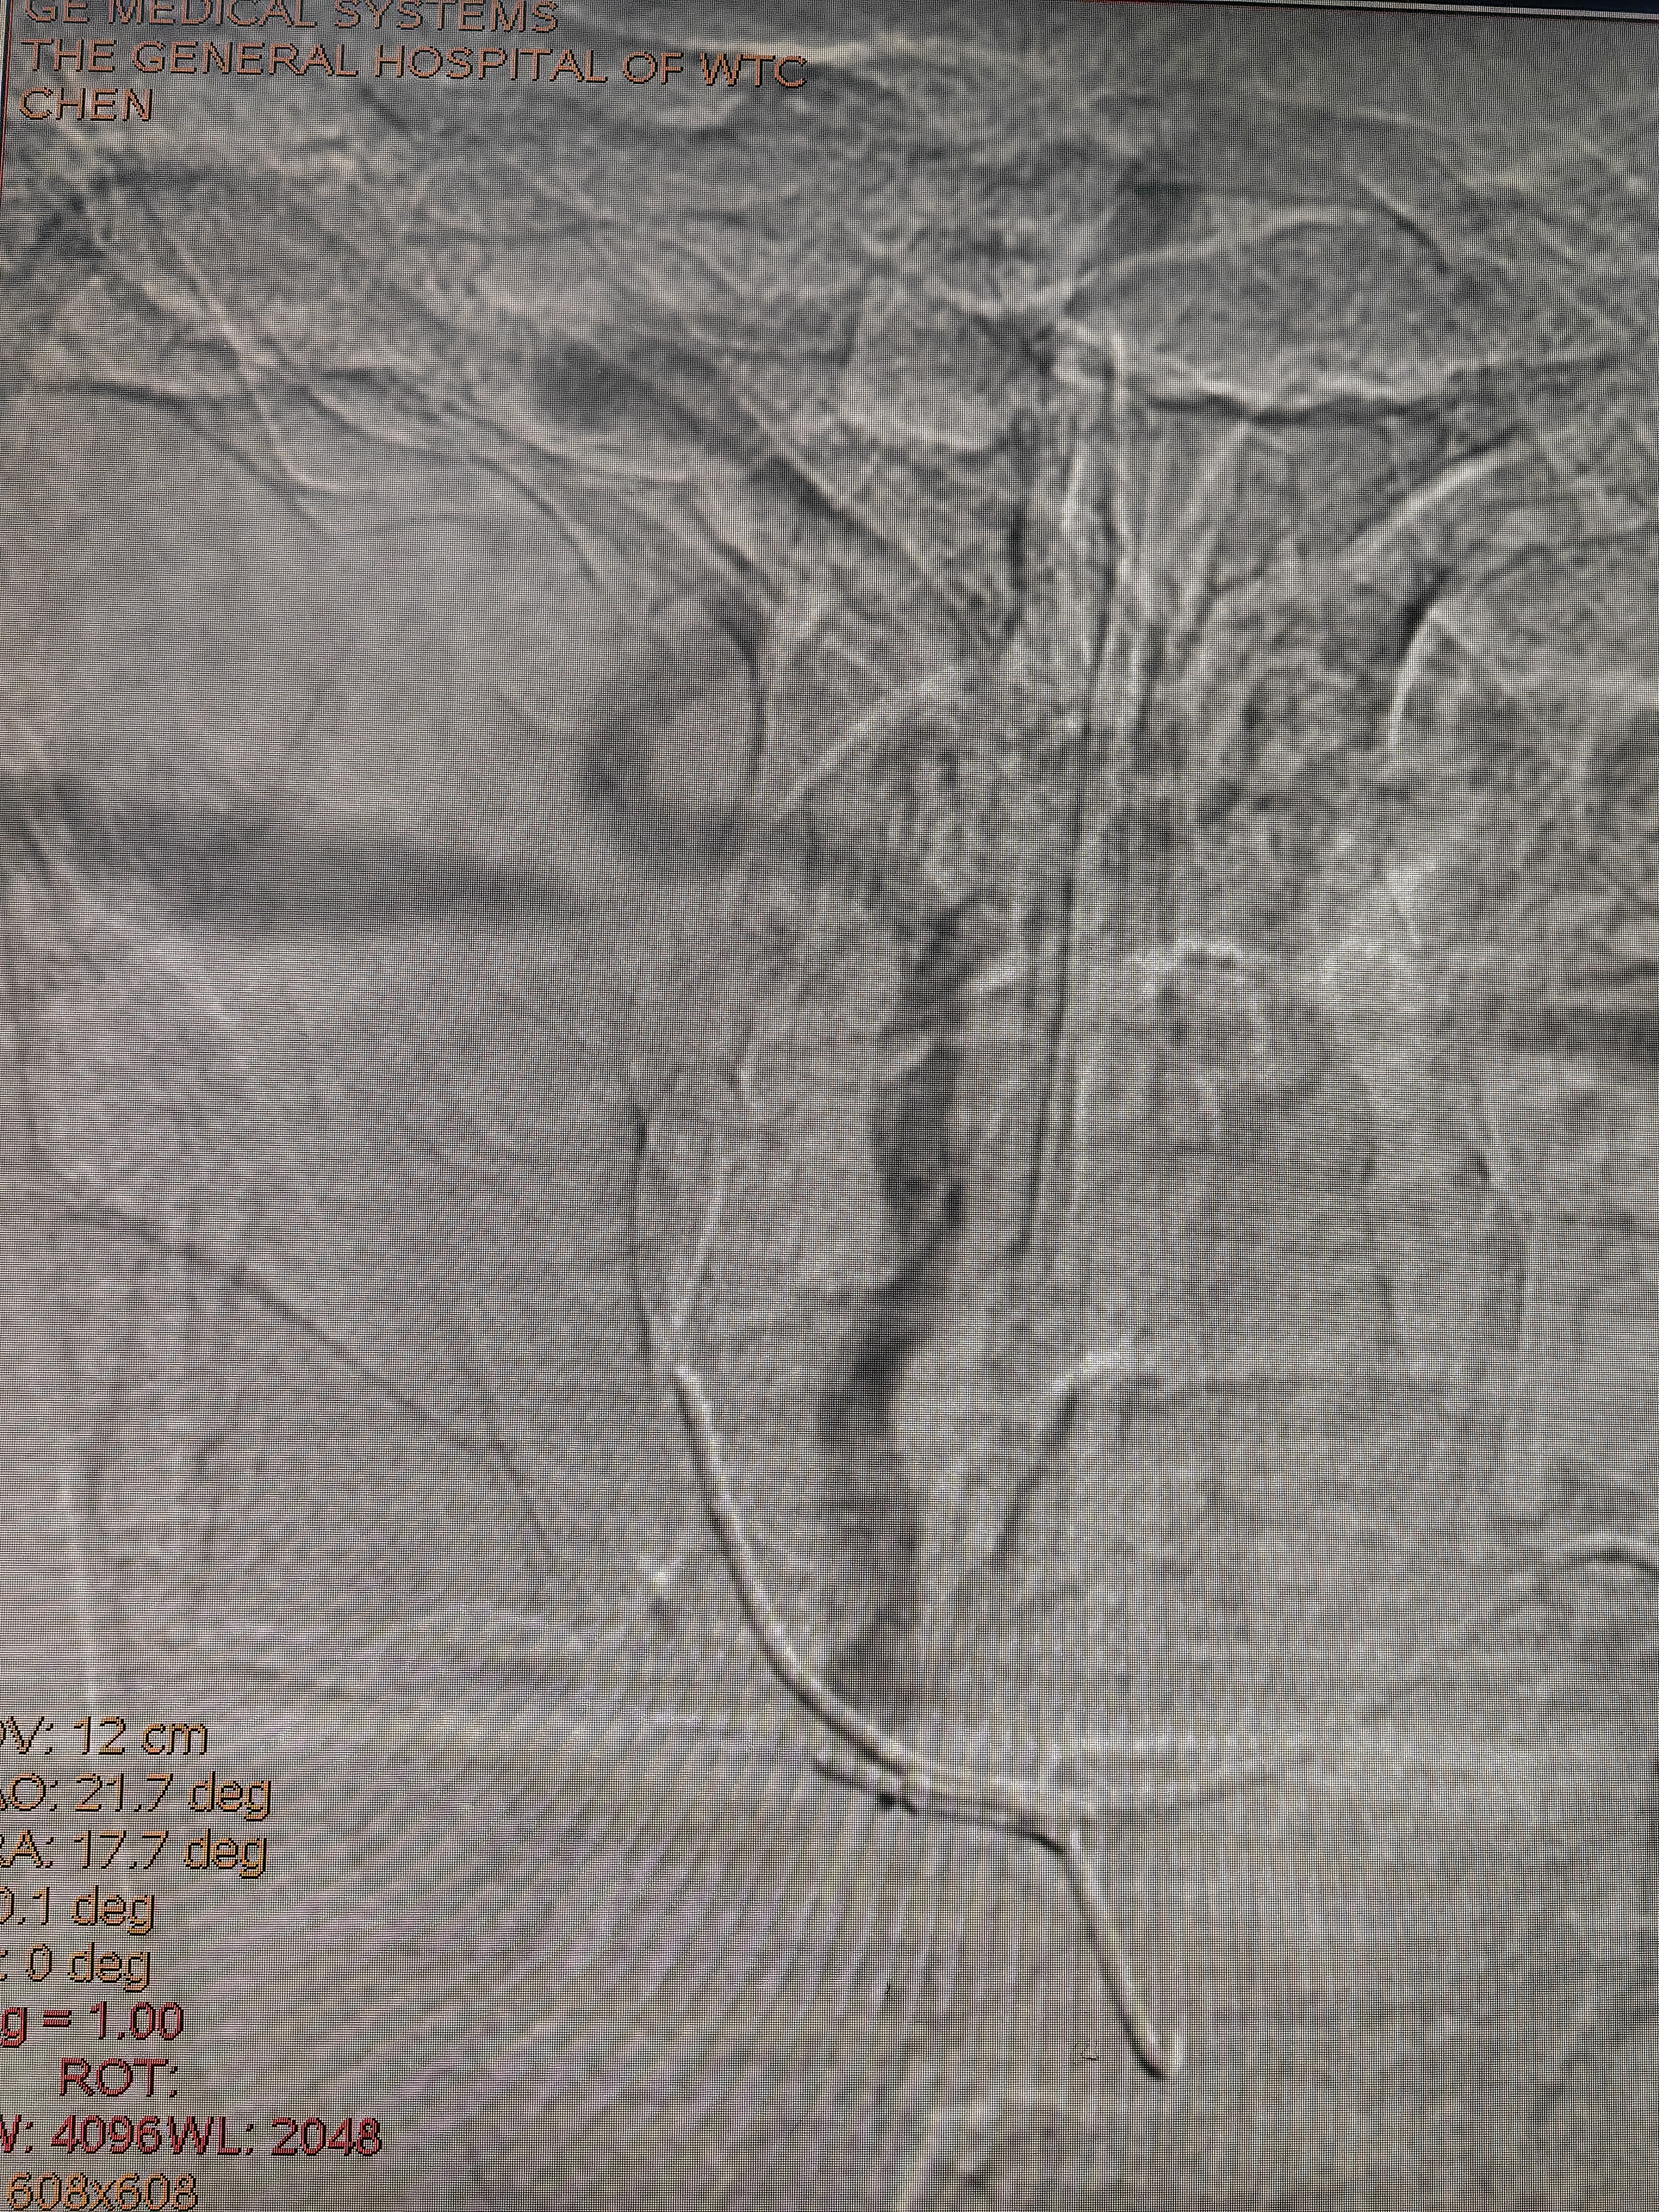

下夜班,手术完成后回家,捧起手机简单汇报一下:中老年女性,后循环小梗死,左侧椎动脉闭塞未见残端,右椎开口次全闭塞。本次计划治疗右椎开口。

接下来的简单了,微导管造影,3m导丝交换,小球囊预扩,支架到位,定位,释放,造影: